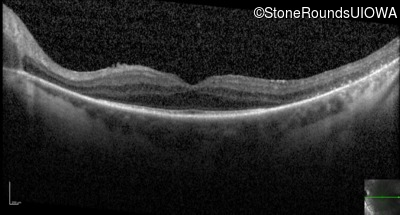

Optical Coherence Tomography - Right - 20/25 -1

Exemplar / OCT Stack

OCT Stack